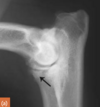

adult irish wolfhound

arrow: sesamoid of m. supinator longus

There is a fractured MCP on the medial aspect of the joint.